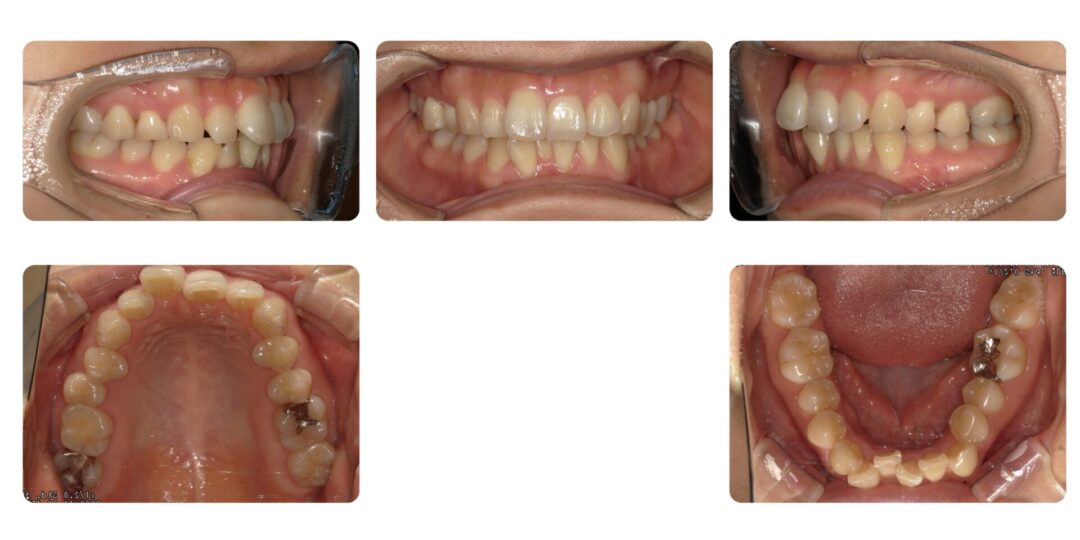

矯正治療後

治療内容

成人矯正 左右第一小臼歯、右下側切歯抜歯 マルチブラケット矯正

治療期間

3年7ヶ月

治療費用

自由診療 基本料金 審美ブラケット¥770,000(初診時)、処置料¥5,500

アンカースクリュー埋入(2本)¥22,000